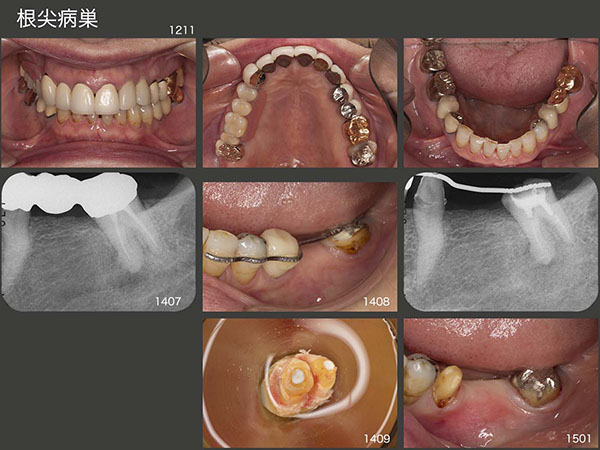

6.根尖病巣

1999年初診,55歳女性.スライド上段3枚は,2012年11月の状態.14年6月,夜間就寝時に左下7に痛みが出たとのことで来院した.デンタルX線写真に以前から根尖病変がみられたが,力の可能性も否定できず,暫く様子をみてもらった.しかし,7月に激痛が生じ,根尖圧痛もみられたため,これは根尖病巣による急性症状と診断した.抗菌剤を投与したのち感染根管治療を数回行ったが,根管が閉鎖しており内科的な治療は不可能と診断した.そこで8月,まず3週間にわたり,左下7の矯正的挺出を行い,抜歯しやすいように細工した.9月,歯の動揺を確認したのちに抜歯を行い,口腔外で滅菌スーパーボンドにより根尖を封鎖した.直ちに元の場所に戻し,隣在歯と3週間固定した.3ヵ月経過を観察し,補綴処置に移行した.

左下は固定式ブリッジでも対応できるが,左下7の予後が心配なため,今回は可撤式ブリッジを選択してもらった.これは将来,もし左下7を失うことがあっても,左下4を支台歯に組み込むことで,片側遊離端義歯に移行できるからである.右上に示す2015年3月のデンタルX線写真から,根尖病変が消失しているのが分かる.20年11月の時点で根尖病変の再発もなく順調に経過している.